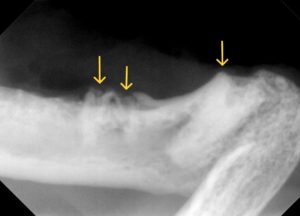

レントゲン検査では、

右上顎臼歯の残根2本と下顎臼歯の残根1本、犬歯は歯冠切除を実施していましたが歯肉に近い場所でした。

レントゲンで確認できる残根を抜歯し、下顎犬歯はより深い場所で切除を実施しました。